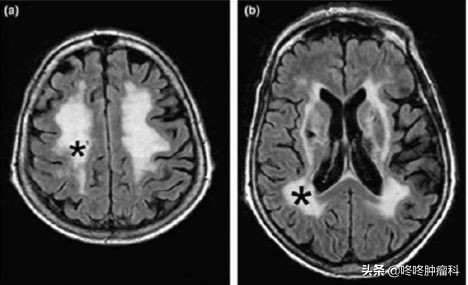

此外,该研究团队还在部分患者的脑部MRI片子上看到了服药一段时间后,脑白质区域出现了明显的异常信号(下图黑色*符号圈出了具体位置)。

与此同时,宫教授带领的团队,也发现相比于服药前,患者长期服药后,右枕叶、左枕叶以及左侧基底节区的脑灰质体积明显下降(下图黄色符号圈出了受影响的区域);既往研究显示:这些区域的脑灰质与认知功能等重要的大脑功能密切相关。